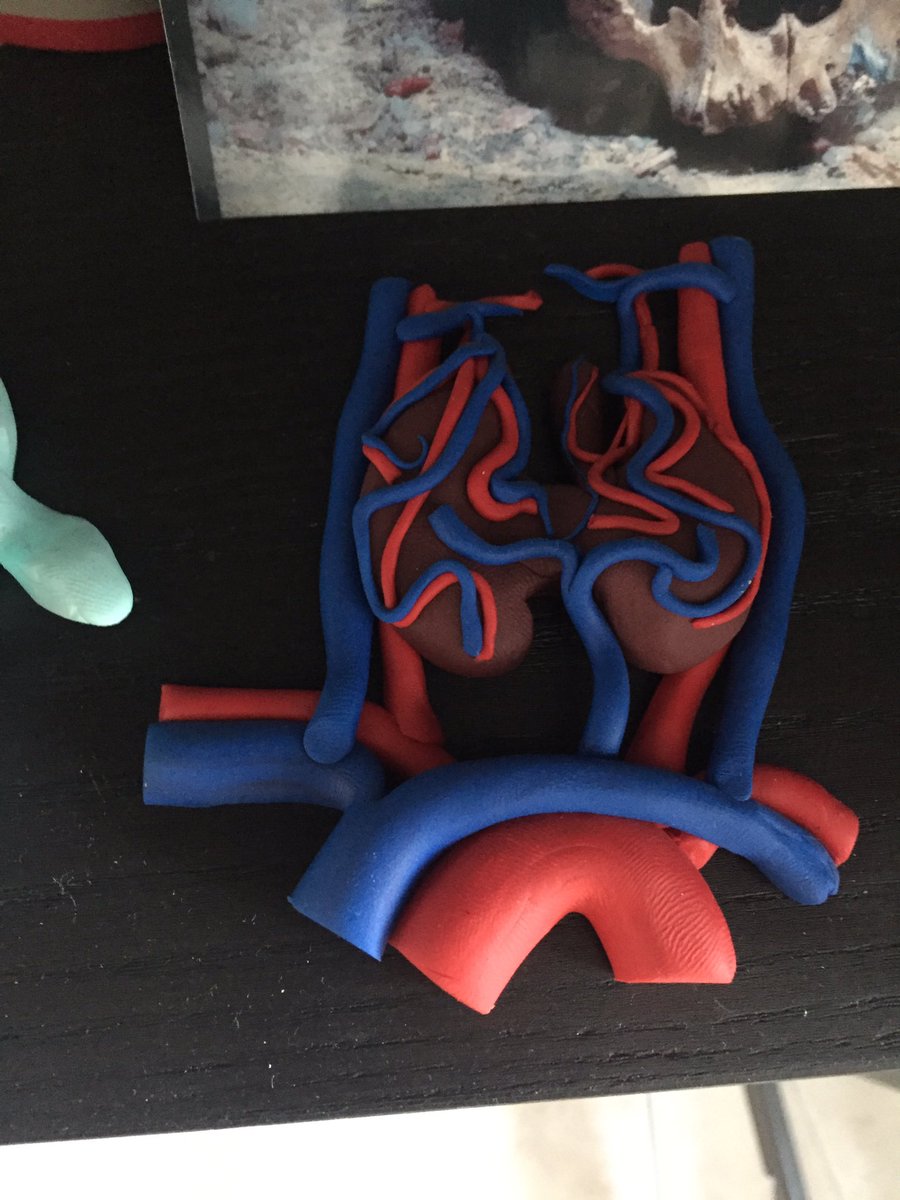

⁉️#GUpath #PEDIpath⚠️ 15YOB with a 7 mm intra testicular nodule... 🔪GROSS🔪 Woo Cheal Cho, MD GU Pathology Society (GUPS) Dr.Gauri Vidolkar MD Frank Ingram, MD Ankur Sangoi @evacomperat Daniel Skipper @AkgulMd Jonathan Zuckerman MD PhD Carla Ellis MD, MS Erasistrate Farshid Siadat, MD, FRCPC Francesca Khani, MD Peter Sadow, MD, PhD Ashish M. Kamat, MD, MBBS Nature Reviews Urology ⏭